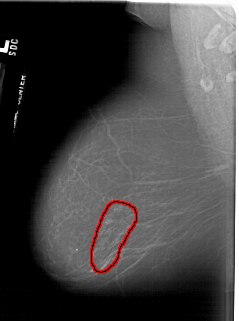

A_1617_1.LEFT_CC

LEFT_CC LINES 6841 PIXELS_PER_LINE 4486 BITS_PER_PIXEL 12 RESOLUTION 43.5 OVERLAY

FILE: A_1617_1.LEFT_CC.OVERLAY

TOTAL_ABNORMALITIES 1

ABNORMALITY 1

LESION_TYPE CALCIFICATION TYPE FINE_LINEAR_BRANCHING DISTRIBUTION SEGMENTAL

ASSESSMENT 5

SUBTLETY 5

PATHOLOGY MALIGNANT

TOTAL_OUTLINES 1